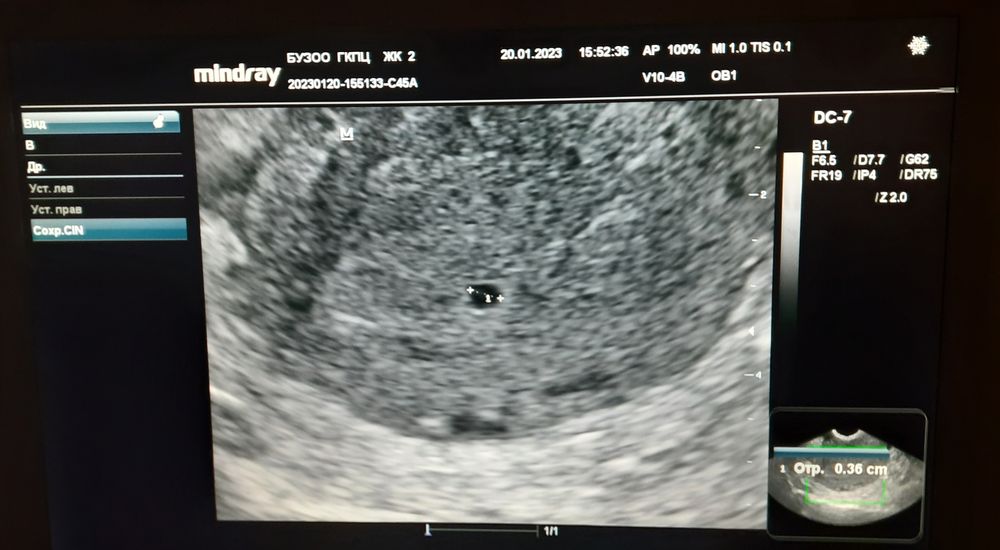

УЗИ, КТГ, доплерСходила на УЗИ. Чтобы подтвердили хотя бы маточную беременность. Итог маточноя беременность малого срока. Желтое тело в левом яичнике ( я так и предполагала по ощущениям). Размер плодного яйца 3,6мм. По месячным 5+3 у меня. Примерно 21-22 ДПО. УЗИ контроль недели через 2 сказали не раньше. Ждём дальше.